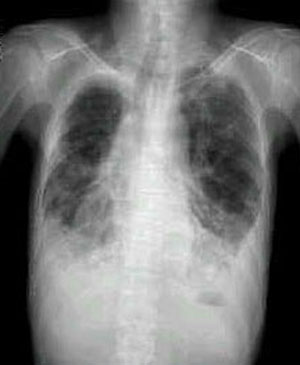

X-선 소견

- 폐문리의 증강과 부정

폐용적의 감소에 의한 폐문리의 집속 : 말초 기 관지의 폐색으로 구역성 또는 폐엽성의 무기폐

진행한 기관지 확장으로 정맥류모양 확장과 낭상 확장초래

대상성 폐기종과 특히 흉막(pleura)비후